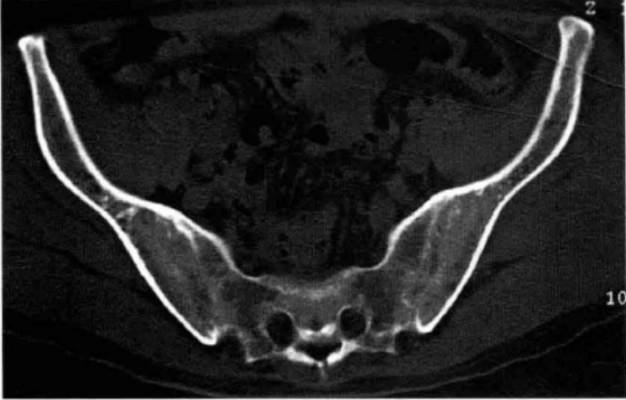

本文图片

X线:颈椎侧位(左)——椎体呈方锥改变 , 前纵韧带骨化;腰椎正位(中、右)——腰椎呈竹节样改变8